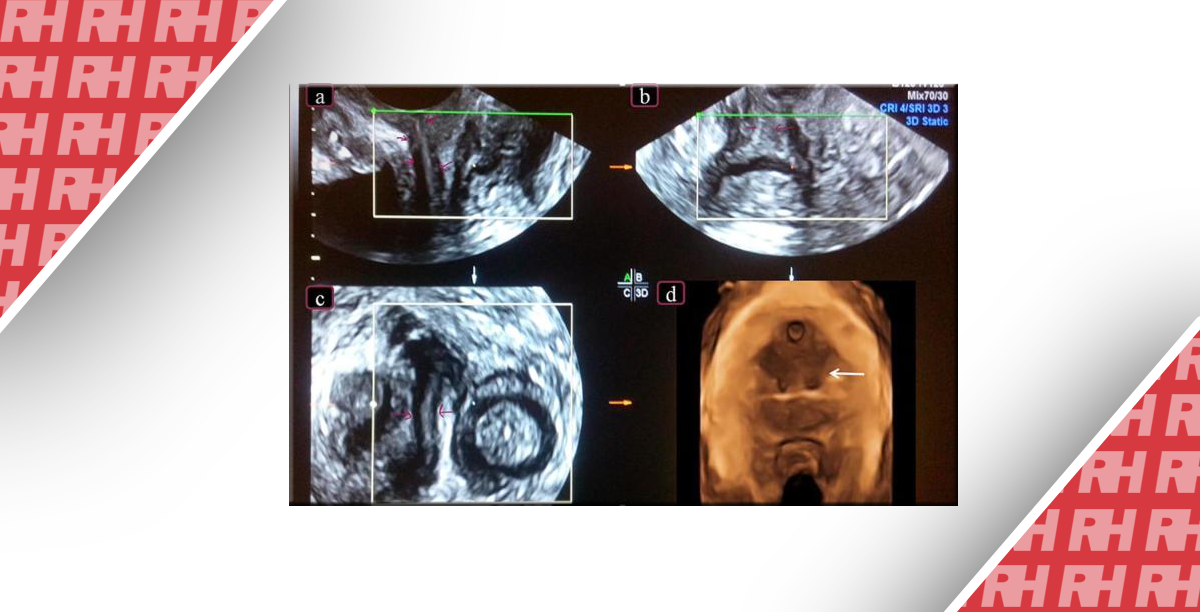

Различают полную перегородку (vagina septa), т. е. такую, когда она доходит до свода влагалища, или неполную, при которой влагалище делится на две части только в определенном его отделе (нижнем, среднем, верхнем, в области сводов — vagina subsepta); чаще всего такая перегородка локализуется в нижней трети влагалища.

В случаях полной влагалищной перегородки могут быть два совершенно обособленных влагалища или одно, разделенное перегородкой на две половицы.

При наличии одновременно и двойной матки с двумя шейками каждая из шеек матки может располагаться в соответствующей половине влагалища; напротив, если имеется одна шейка матки, то она может располагаться в одной из половин влагалища. Влагалищная перегородка реже располагается в поперечном направлении и делит влагалищный канал как бы на два этажа.

При наличии перегородки по всей длине влагалищной трубки или только в верхнем отделе его (в области переднего или заднего сводов), как правило, имеет место и раздвоение матки — двурогая, двушеечная, двойная матка и другие пороки развития.